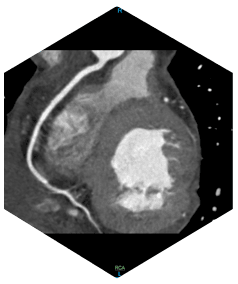

128-Zeilen-CT: Entwickelt für

Herzuntersuchungen

» Schneller 0,25-Sekunden-Herzscan

» EKG im Gantry integriert »

46 ms zeitliche Auflösung des Herzens »

Prospektive oder retrospektive Eingabe mit

bis zu vier Sektoren